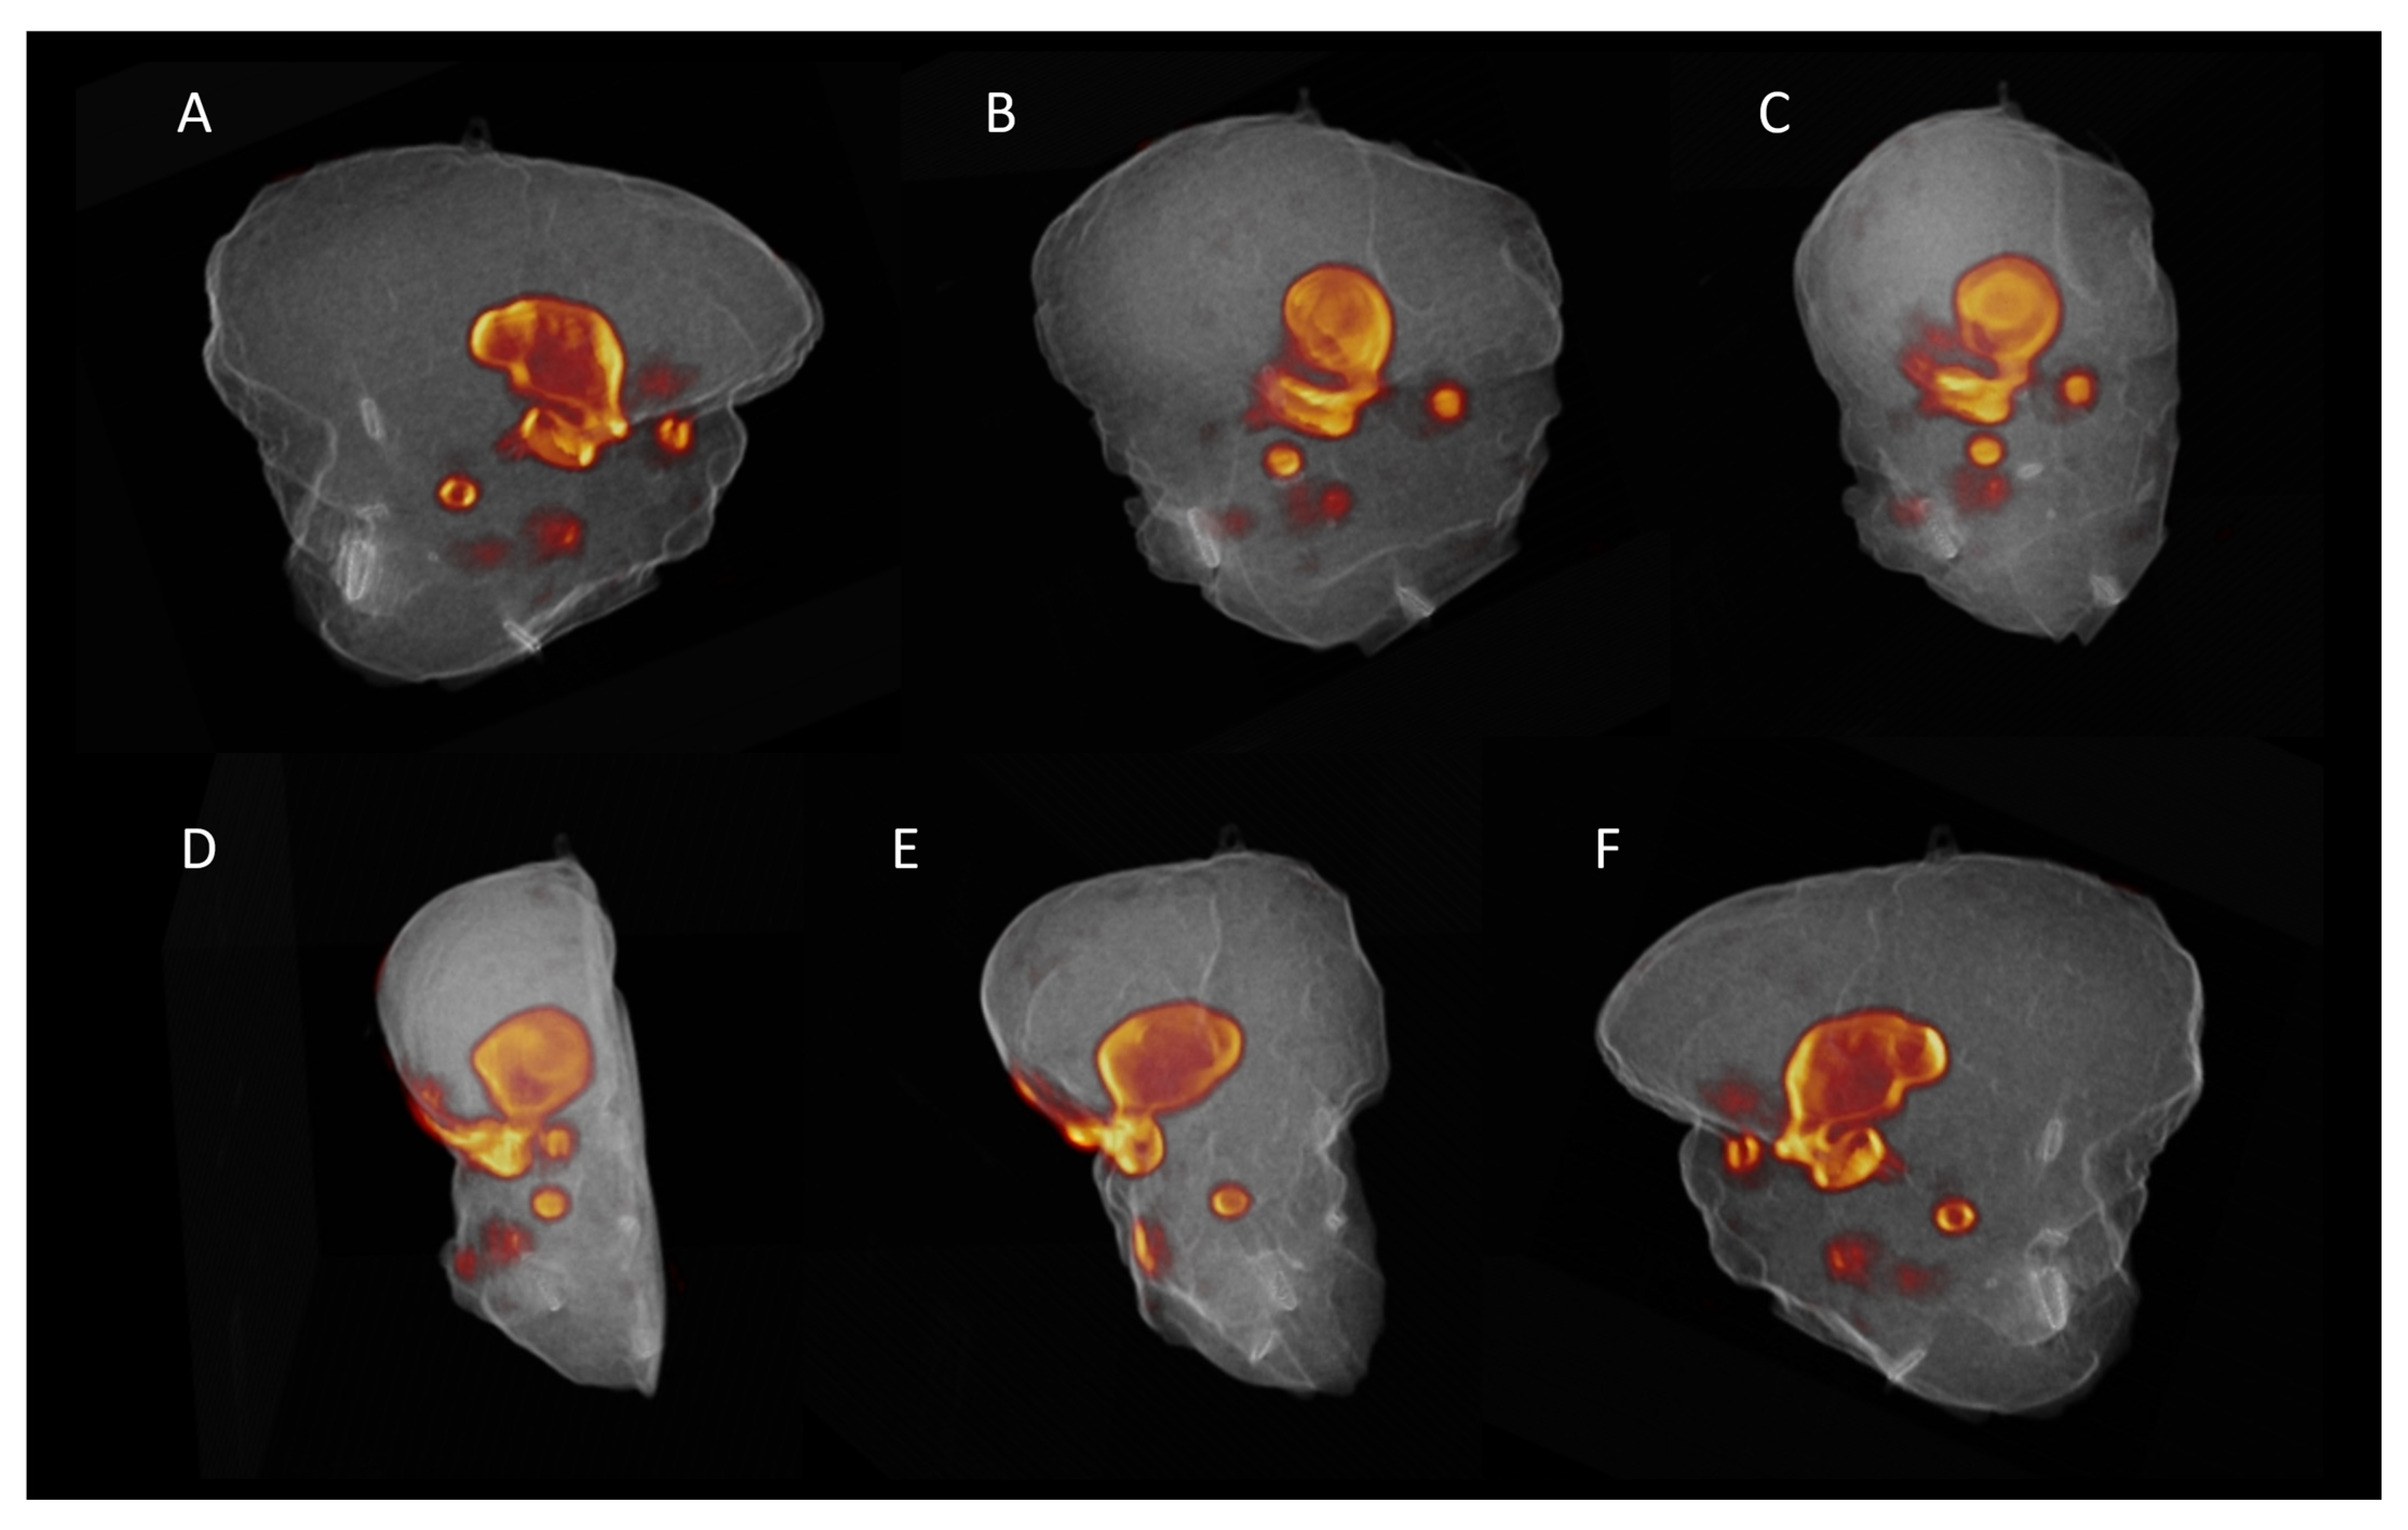

3.2. Ex Vivo Specimen PET/CT

3.3. Pathology and Correlation with the Imaging Results

3.4. Lymph Nodes